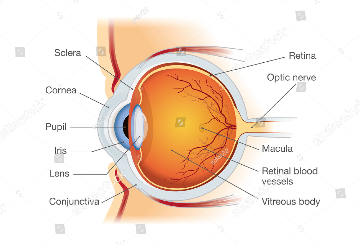

2021年眼外科最新国际会议(ICESU )